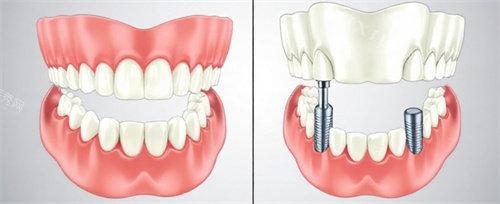

在医生团队方面,姚赞斌口腔汇聚了一批经验充足、技艺娴熟的口腔医师 。这些医生均毕业于出名口腔院校,经过多年临床实践,积累了大量种植牙成功实例。无论是单颗牙缺失、多颗牙缺失,还是全口牙缺失的种植修复,医生们都能凭借扎实的正规知识和丰富的操作经验,根据患者牙槽骨状况、邻牙情况等个体差异,制定个性化种植方案。比如针对牙槽骨骨量不足的患者,医生会采用骨增量技术,为种植牙创造良好条件,确保种植成功概率。

在多颗牙缺失或全口牙缺失的种植修复上,姚赞斌口腔也推出了相应套餐优惠活动。半口种植牙如果采用较为经济实惠的种植方案,费用大概在 20000 - 30000 元;全口种植牙套餐价格则在 40000 - 60000 元区间 。并且,该口腔机构收费透明,不存在隐形消费,患者在治疗前就能清晰知晓各项费用明细,从种植体、基台到牙冠,每一项费用都明确列出,让患者消费得明明白白。